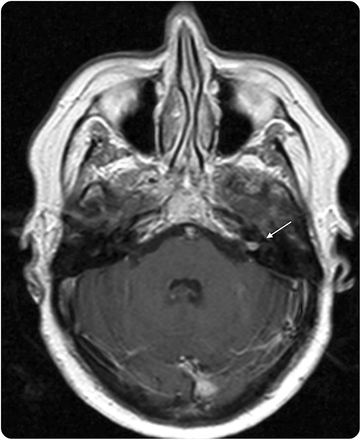

一个59岁的女人面对进步奔袭感音神经性听力损失。检查显示一个增强病灶内部听觉运河(IAC)符合前庭神经鞘瘤(图1)。

病人接受了translabyrinthine方法切除的质量。IAC的硬脑膜打开的时候,没有发现肿瘤,但几家大型船只被指出。

执行脑血管造影术和早期静脉引流动静脉瘘的建议,美联储前下小脑动脉,排入优越伪劣坚硬的鼻窦(图2)。